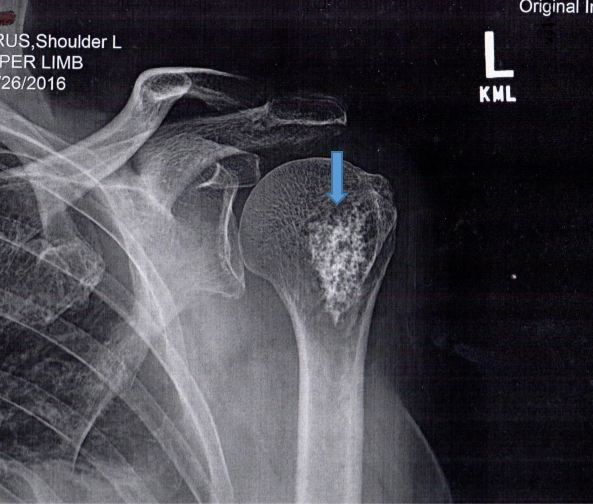

Based on the appearance of the lytic lesion in this patient, the orthopedic physician’s clinical judgement was that it was benign. Consequently, he repeated the radiographs (Figure 2). Even though the chance of malignancy (low-grade chondrosarcoma) is approximately 1%, this patient had noncontrast CT (Figure 3) and MRI (Figure 4) scans.

Figure 2. Anteroposterior radiograph of the left proximal humerus and shoulder. Note: 5-cm calcified lesion (arrow) without evidence of cortical erosion. The tumor margins are sharp and the “popcorn” appearance of calcified cartilage is typical of enchondroma.